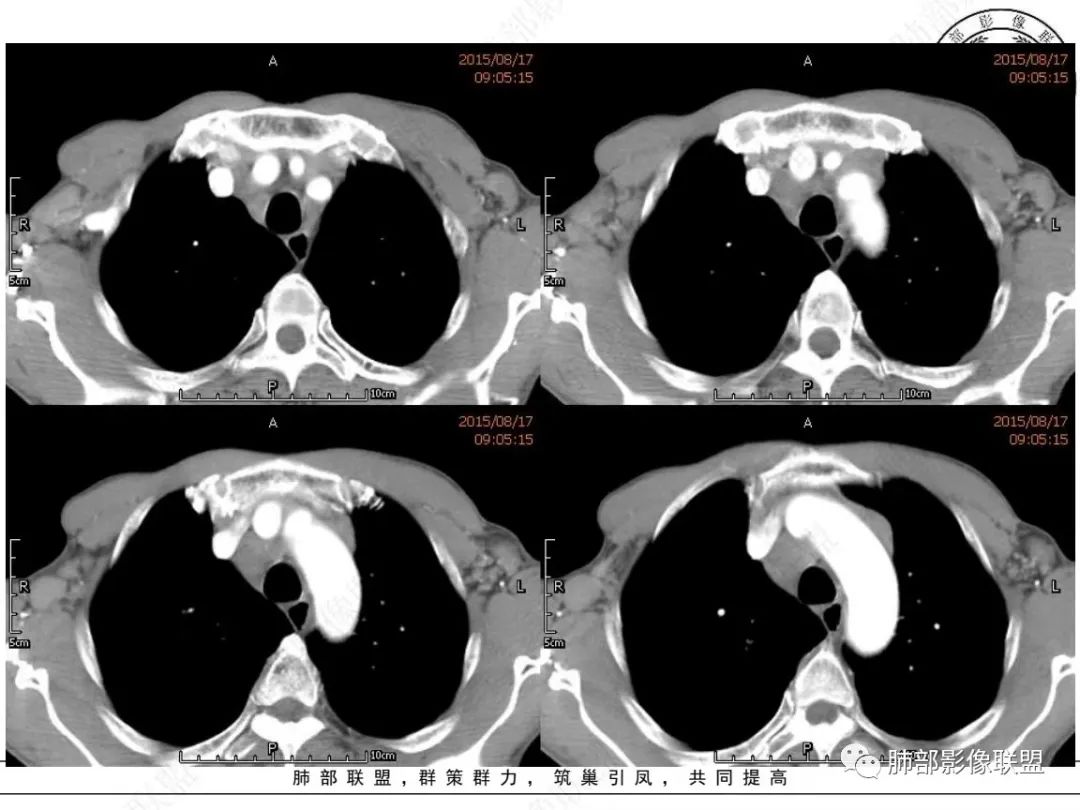

崔少钢:老年男性,有吸烟史,右肺下叶背段示小结节,纵隔、腋窝及右肺门淋巴结节肿大,气管受压狭窄,后纵隔软组织内示血管走行,考虑小细胞>淋巴瘤。

我只是邓较瘦:晨读老年男性,长期吸烟。右肺门、纵隔多发肿大淋巴结、融合成团块,中间支气管、右肺下叶支气管受压变窄,增强扫描强化程度较轻,血管包埋。另两侧腋窝亦见多发肿大淋巴结。常规恶性没问题,小细胞?淋巴瘤?但是於老师的病例总感觉没那么简单。

MCL的CT表现为分布无规律的全身多区域淋巴结受侵,少有单一区域淋巴结受累,结外器官受侵多见;MCL有一般NHL淋巴结受累基本CT表现,平扫CT表现为病变密度均匀,受累淋巴结区内呈融合状生长,边界清楚,增强后病灶呈均匀、中等强化,一般病变内无低密度坏死区。确诊需要病理及免疫组化,根据肿瘤组织形态学和免疫组织化学 CD5 及cyclin D1 的表达绝大多数 MCL 可做出明确病理诊。

1.小细胞肺CA:好发吸烟老年男性。常有血液NSE及胃泌素释放肽前体升高。Syn、CgA、CD56阳性。其CT特点可有:冰冻纵隔、冰冻肺门。血管包埋征。针尖样支气管。鸭蹼状凸起。娘小崽大。脂肪间隙消失(常指纵隔及肺门内)。阻塞性炎症不重。侵袭性强。破坏力不强。收缩力弱,内无空泡。沼泽样强化,坏死散而小,坏死不彻底,强化偏低。表面圆钝,角状及条状凸起,蠕虫样表现,腊肠样尾巴(朝肺门侧或背离肺门侧均可以)。胸水多“清澈”(可以理解为淋巴液回流障碍导致的胸水)。点簇状钙化(类似盐与胡椒样)。多见癌性淋巴管炎。另外黄勇老师提出胸膜下的小细胞肺癌具有“山丘征”的特点。